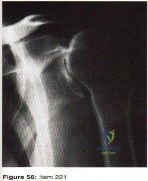

- Associated displaced surgical neck fracture of the humerus

- humeral arthroplasty

2/. repair of the rotator cuff

- closed reduction and immobilization

- open reduction and immobilization

- open reduction and early passive motion

- Injury to the subclavian artery

- Injury to the brachial plexus

- Segmental fracture

- 100% displacement

- Associated displaced surgical neck fracture of the humerus

- humeral arthroplasty

2/. repair of the rotator cuff

- closed reduction and immobilization

- open reduction and immobilization

- open reduction and early passive motion